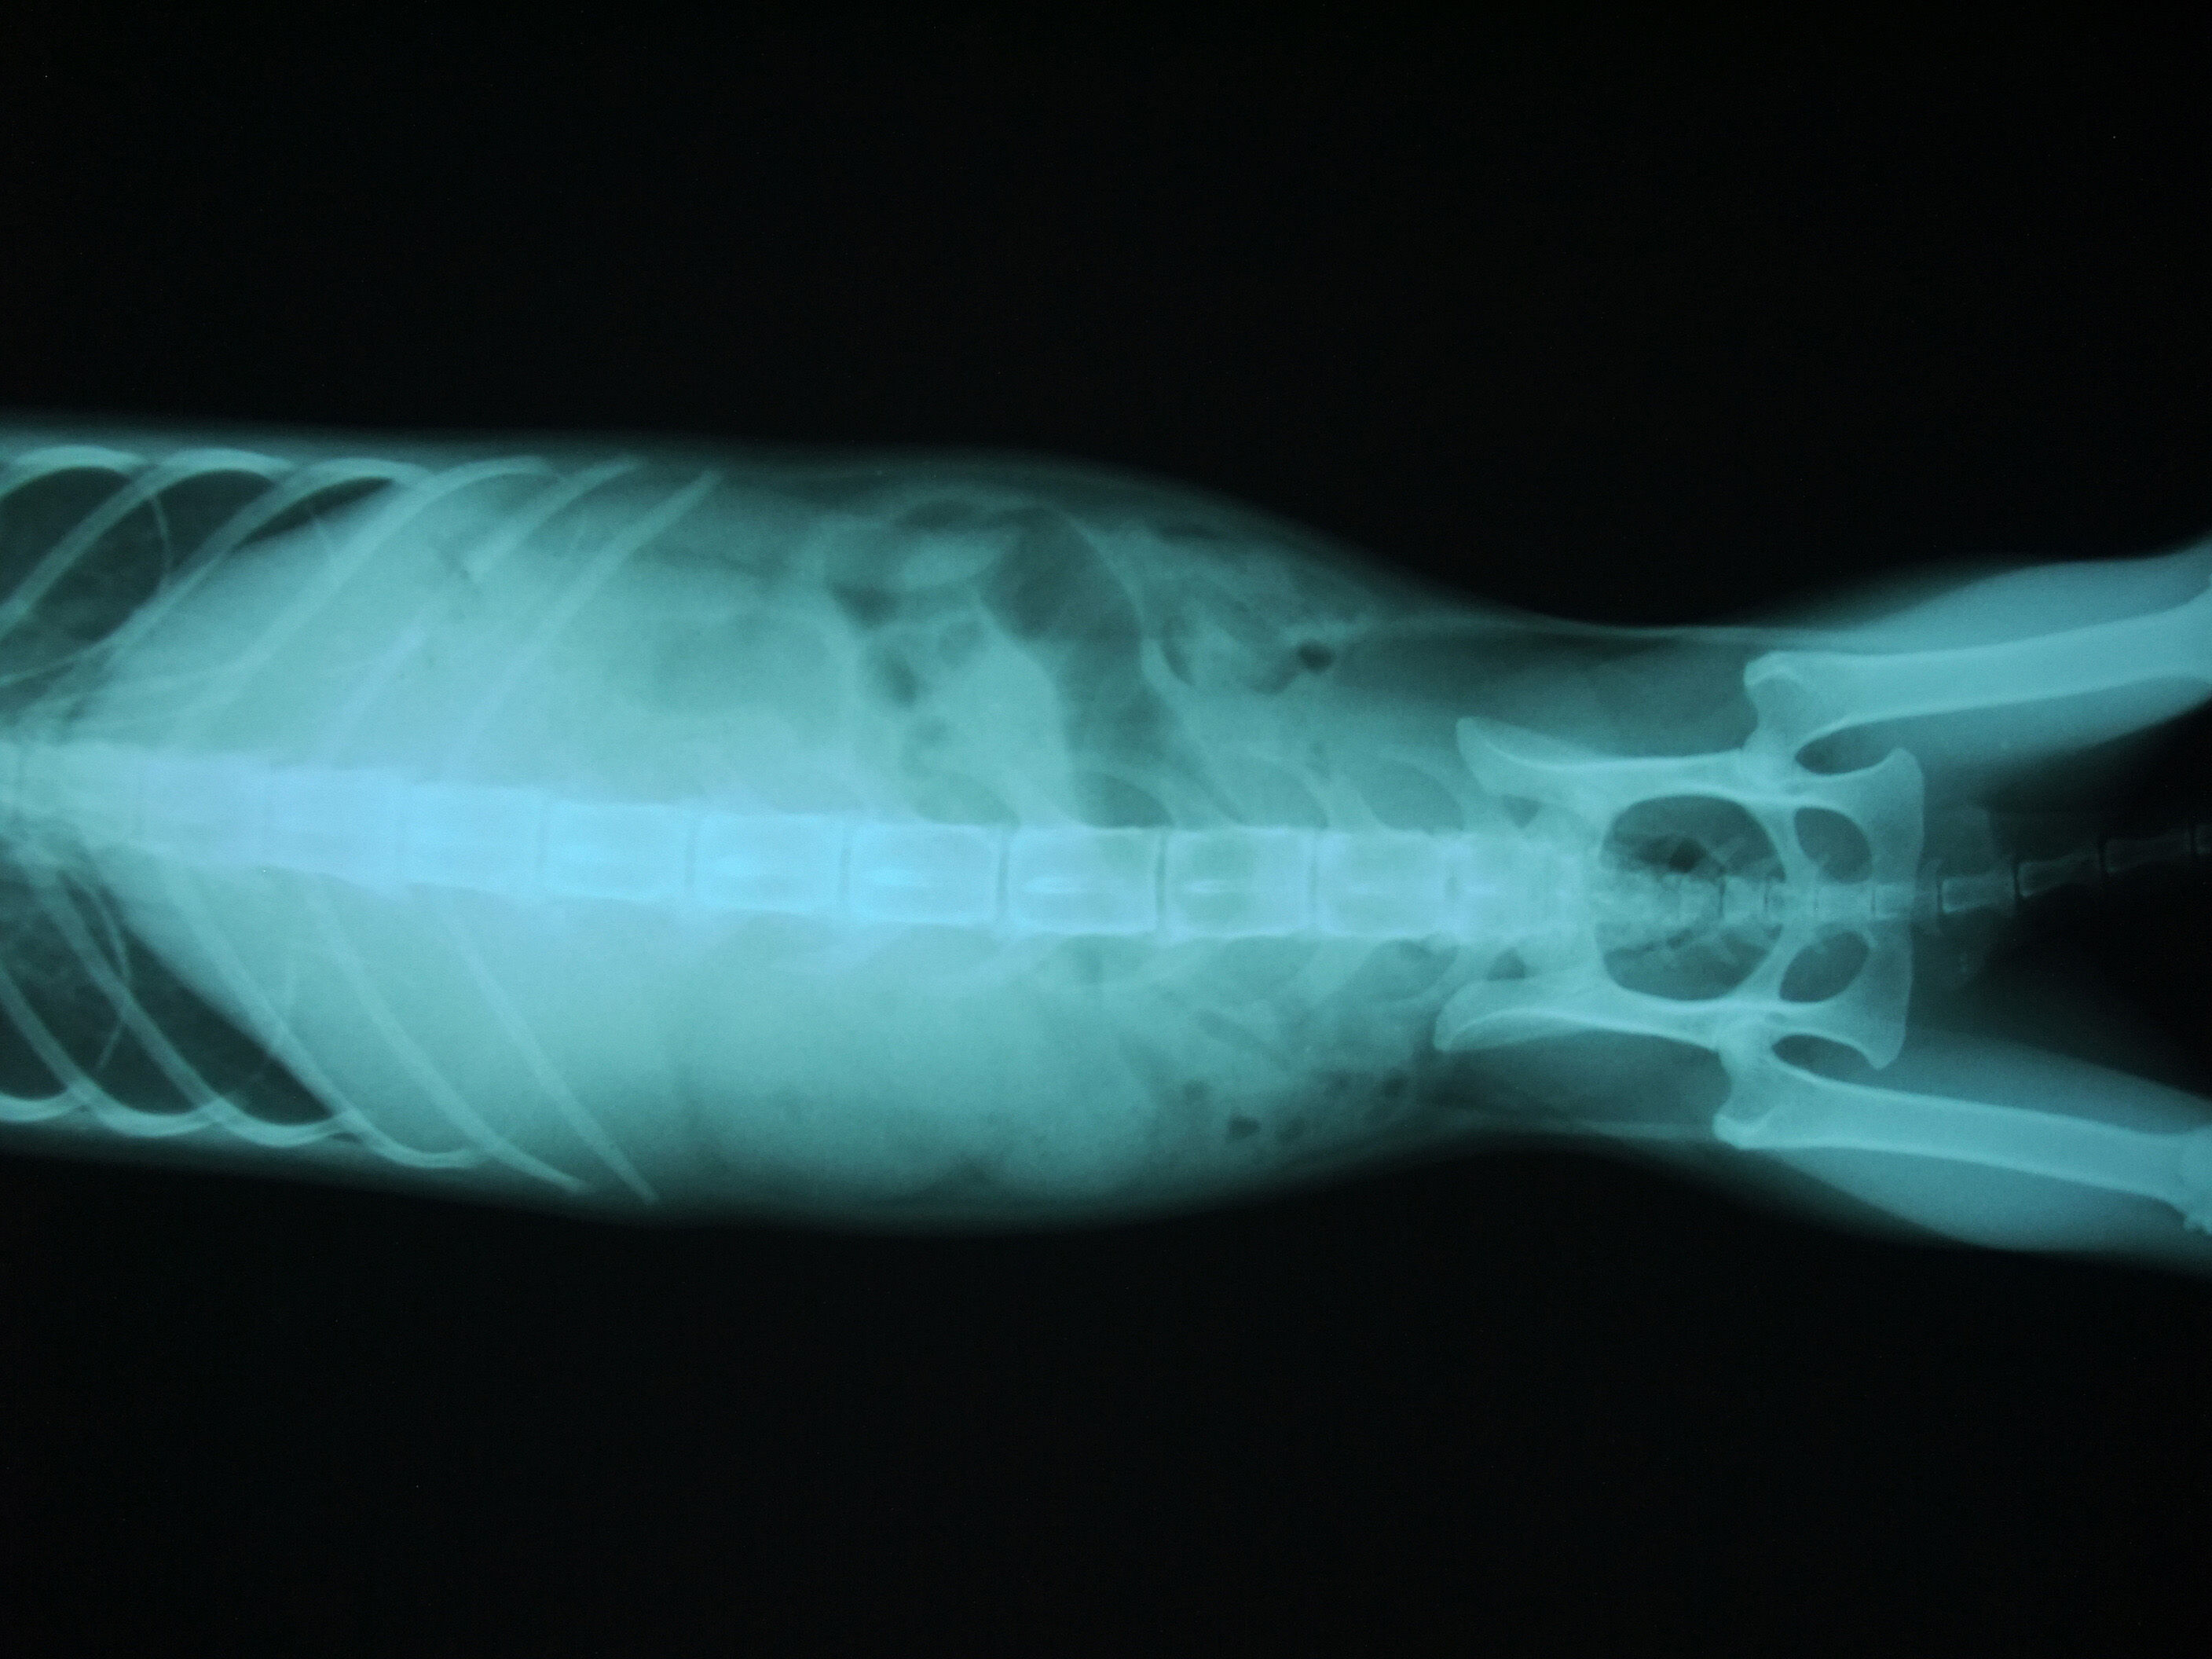

幾天後,腎指數有稍微的下降,但還是高的驚人,所以醫生拍了X光確認,我們看到,一顆腎臟已萎縮,一顆則異常的腫大。醫生說,因萎縮的腎臟已失去功能,所以造成另一顆腎臟過度使用,但不代表它的運作功能是正常的。